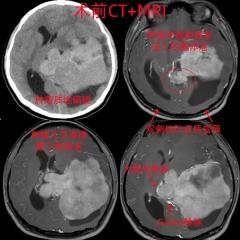

早高峰车祸重伤 西安国际医学中心医院多学科接力上演生死时速